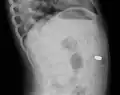

AP X ray showing a 9mm battery in the intestines -

Lateral X ray showing a 9mm battery in the intestines -